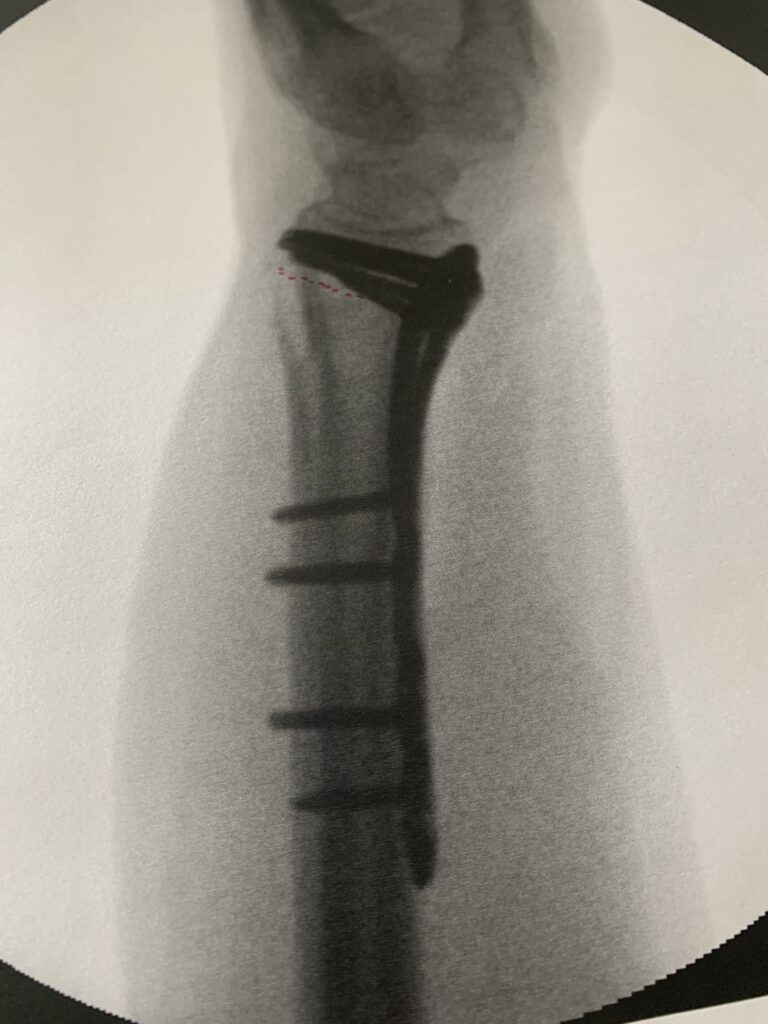

Die Folgen allerdings gravierend. Zwischenzeitlich bin ich stolzer (?) Besitzer eines Krokodils, welches die zerbröselten Knochenteile im Handgelenk mit einer grossen Portion Schrauben zusammen hält.

Dankbar auch für die moderne Medizin, die es mir auch als Laie ermöglicht hat, dank modernster Diagnostik zu begreifen, WAS da eigentlich kaputt, zerbröselt und verschoben. Ich meine dieses Bild…

.. ist doch der Hammer! Und dankbar bin ich auch, dass ich blitzartig in fachlich geschulte Hände kam, die mich mit entschmerzten und nach bestem Wissen und Gewissen zusammen geflickt haben. Jetzt hocke ich artig auf dem Sofa und genese!